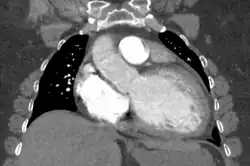

Generalized enlargement of the heart is seen upon normal chest X-ray. Pleural effusion may also be noticed, which is due to pulmonary venous hypertension.[28]

The electrocardiogram often shows sinus tachycardia or atrial fibrillation, ventricular arrhythmias, left atrial enlargement, and sometimes intraventricular conduction defects and low voltage. When left bundle-branch block (LBBB) is accompanied by right axis deviation (RAD), the rare combination is considered to be highly suggestive of dilated or congestive cardiomyopathy.[29][30] Echocardiogram shows left ventricular dilatation with normal or thinned walls and reduced ejection fraction. Cardiac catheterization and coronary angiography are often performed to exclude ischemic heart disease.[28]